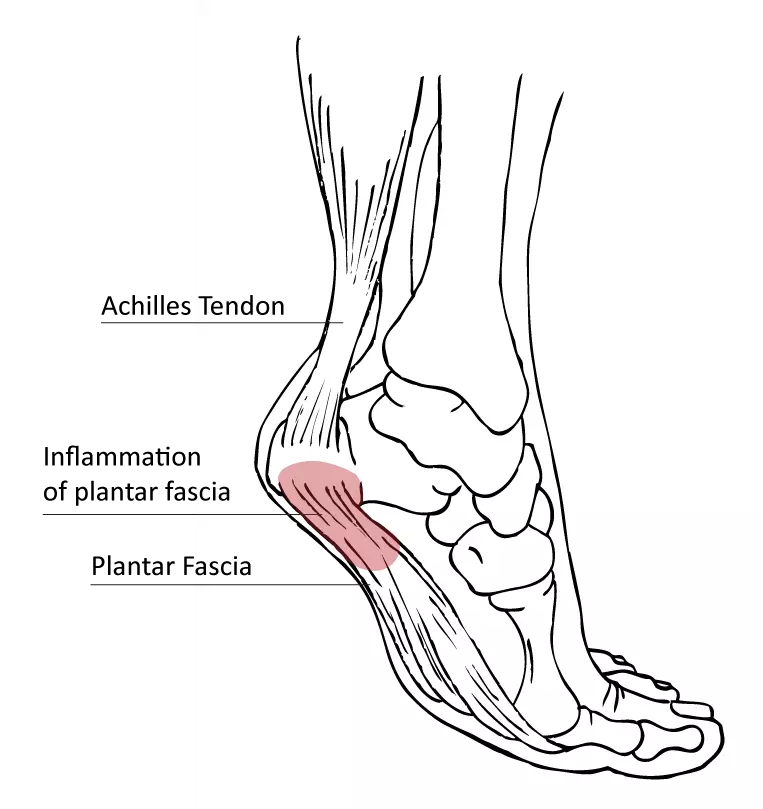

Plantar fasciitis and achilles pain clearance

Plantar fasciitis and achilles pain clearance, Is My Heel Pain Achilles Tendonitis vs Plantar Fasciitis Ease Achilles Heel Pain With These Tips clearance

Plantar fasciitis and achilles pain clearance

Achilles Tendonitis vs. Plantar Fasciitis Which Do I Have Arlington Mansfield Foot Ankle Centers Podiatrists clearance, plantar fasciitis clearance, Heel Pain Causes and Treatment clearance, Achilles Tendon Pain and Plantar Fasciitis Treatment Guide clearance, This Stretch Relieves Plantar Fasciitis Shin Splints Achilles Pain and Heel Pain Focusphysiotherapy clearance, Heel Pain Plantar Fasciitis Delaware Foot and Ankle Group Podiatrist in Newark DE clearance, Plantar Fasciitis and Achilles Tendonopathy InterX Pain Clinic Stratford Upon Avon clearance, Heel Pain Podiatrist Temple Hill Clinton MD Burton J. Katzen DPM clearance, Back of Achilles Tendon Heel Pain Shoes Orthotics Home Treatment clearance, Seattle Bellevue Heel Pain Center Issaquah Foot Ankle Specialists clearance, Interwoven Threads The Plantar Fascia Achilles Tendon Connection clearance, Plantar fasciitis VS Achilles tendinitis Managing Heel Pain Greg Robinson Ibraheem Podiatry clearance, Can Plantar Fasciitis Cause Calf Pain clearance, Plantar fasciitis achilles tendon deals pain clearance, On the morphological relations of the Achilles tendon and plantar fascia via the calcaneus a cadaveric study Scientific Reports clearance, This One Stretch Helps Relieve Plantar Fasciitis Shin Splints Achilles Pain and Heel Pain clearance, Plantar Fasciitis Symptoms and Treatment Doctor clearance, Effective Treatment for Heel Pain Foot Foundation clearance, Plantar Fasciitis Chiropractors in Newmarket ON clearance, Plantar Fasciitis FAQ s clearance, Plantar Fasciitis Symptoms Causes Treatment Options clearance, Is My Heel Pain Achilles Tendonitis vs Plantar Fasciitis Ease Achilles Heel Pain With These Tips clearance, Plantar fasciitis Information Mount Sinai New York clearance, Achilles Tendonitis Plantar Fasciitis clearance, Common Problems that Can Lead to Plantar Fasciitis and Achilles Tendonitis clearance, Heel Pain clearance, Is Plantar Fasciitis Your Achilles Heel Prosper clearance, Plantar Fasciitis Dr7 Physiotherapy Podiatry Hydrotherapy Massage clearance, Foot or Heel Pain It Might Be Plantar Fasciitis Healthy You clearance, Achilles Tendonitis and Plantar Fasciitis Premier Podiatry Velimir Petkov DPM Podiatrists clearance, Achilles Tendonitis Vs Plantar Fasciitis Which Do I Have clearance, Difference between Plantar Fasciitis and Achilles Tendonitis Achieve clearance, Achilles Tendonitis vs. Plantar Fasciitis clearance, Achilles tendonitis vs. plantar fasciitis How to tell the difference clearance, Achilles tendonitis vs. plantar fasciitis How to tell the difference clearance, Product Info: Plantar fasciitis and achilles pain clearance.

Plantar fasciitis and achilles pain clearance

Plantar Fasciitis Symptoms and Treatment Doctor- plantar fasciitis and achilles pain